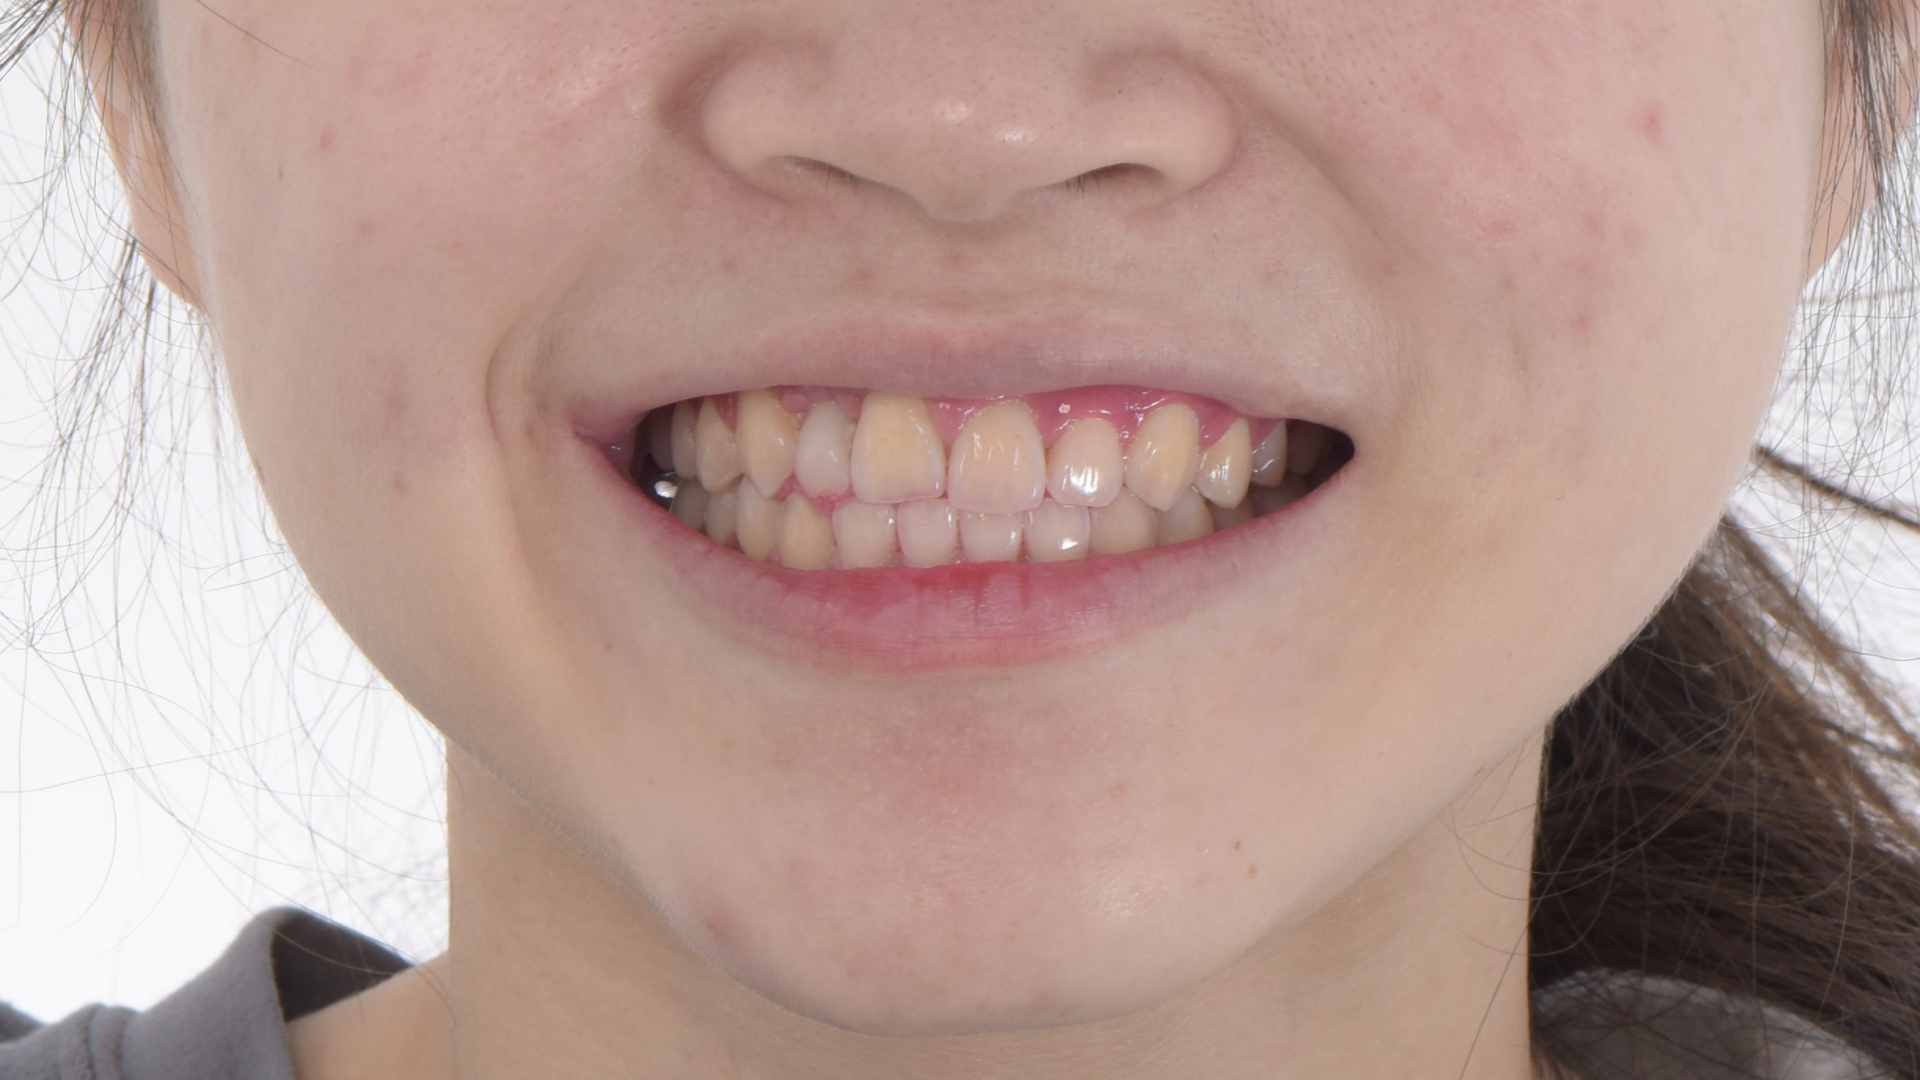

治療前牙齒因車禍有縫且缺牙